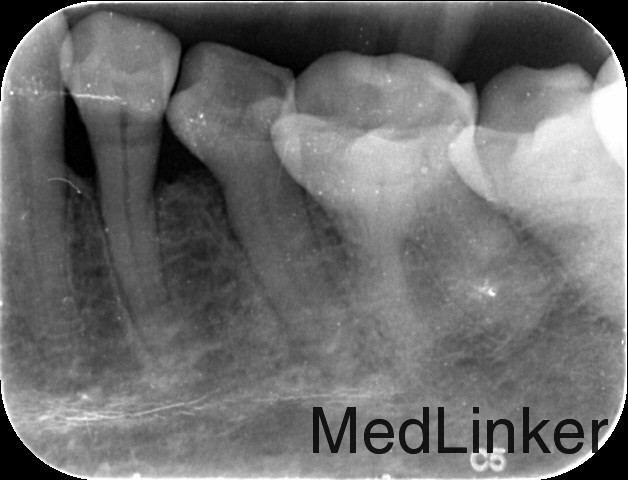

检查: 35合面见牙色充填物,探边缘密合,叩痛(+),松动I度,牙龈轻度红肿。 X线示:35根管内见致密根充影像,牙根根上、中1/3交界处连续性中断。

诊断:35根折 治疗计划:35拔除 治疗:35局部消毒,碧兰麻局部麻醉下,挺松拔除,搔刮牙槽窝,复位,局部压迫止血。常规拔牙后医嘱。 建议:修复科制定全口缺失牙修复计划